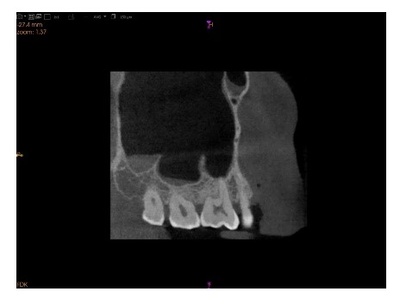

Diagnosis in pediatric dentistry plays a vital role in the treatment of dental diseases and the prevention of their complications. Regarding the AI application, ChatGPT and POE’s diagnostic models are being proposed for pediatric diagnosis. To assess the accuracy of two AI programs in diagnosing pediatric cases. To compare POE and ChatGPT and to evaluate the completeness of the responses generated by each AI program. This is a retrospective study comparing the accuracy of two AI programs in diag